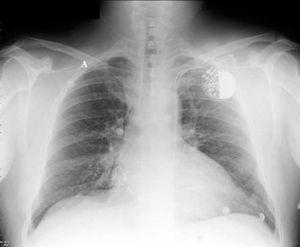

Paciente varón, de 44 años de edad, sometido a implante de marcapasos definitivo debido a un bloqueo aurículo-ventricular de tercer grado, de causa desconocida al no tomar medicación concomitante que pudiera explicar el trastorno de la conducción, ni tener antecedentes clínicos que pudieran justificarlo. Durante el implante los electrodos auricular y ventricular son introducidos a través de la vena subclavia izquierda, y se observa en la escopia que ambos avanzan en dirección caudal por el borde paraesternal izquierdo, confirmándose esta posición en la radiografía posteroanterior de tórax (fig. 1). Los electrodos se encuentran implantados en la aurícula derecha y ventrículo derecho, la amplitud de los sensados y umbrales es correcta. Algunos días más tarde se realiza tomografía axial computarizada torácica (fig. 2), que muestra la vena cava superior (flecha pequeña) y una vena cava superior izquierda (flecha grande), conteniendo ésta última ambos electrodos en su interior.

Figura 1. Radiografía postero-anterior de tórax, mostrando los electrodos de marcapasos que descienden por el borde esternal izquierdo, encontrándose alojados en aurícula y ventrículo derechos.